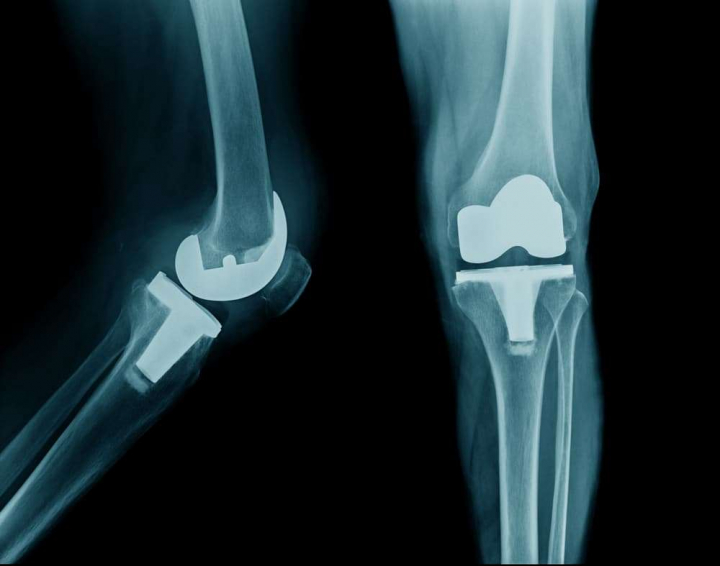

Данное исследование проведено с целью определения эффективности 3-месячной программы лечения, состоящей из нейромышечной тренировки, образовательных мероприятий, диеты, применения специальных стелек и обезболивающих препаратов (лечение по схеме MEDIC), по сравнению с обычной схемой лечения (два информационных лифлета для пациентов и советы по лечению) по степени снижения оценок боли и сенсибилизации у пациентов с остеоартритом коленного сустава (ОА), которым не может быть проведено тотальное эндопротезирование коленного сустава (ТЭКС).